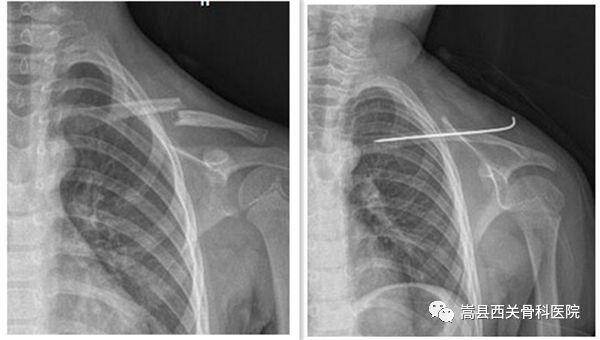

我院上肢创伤科部分患者术前术后对比图